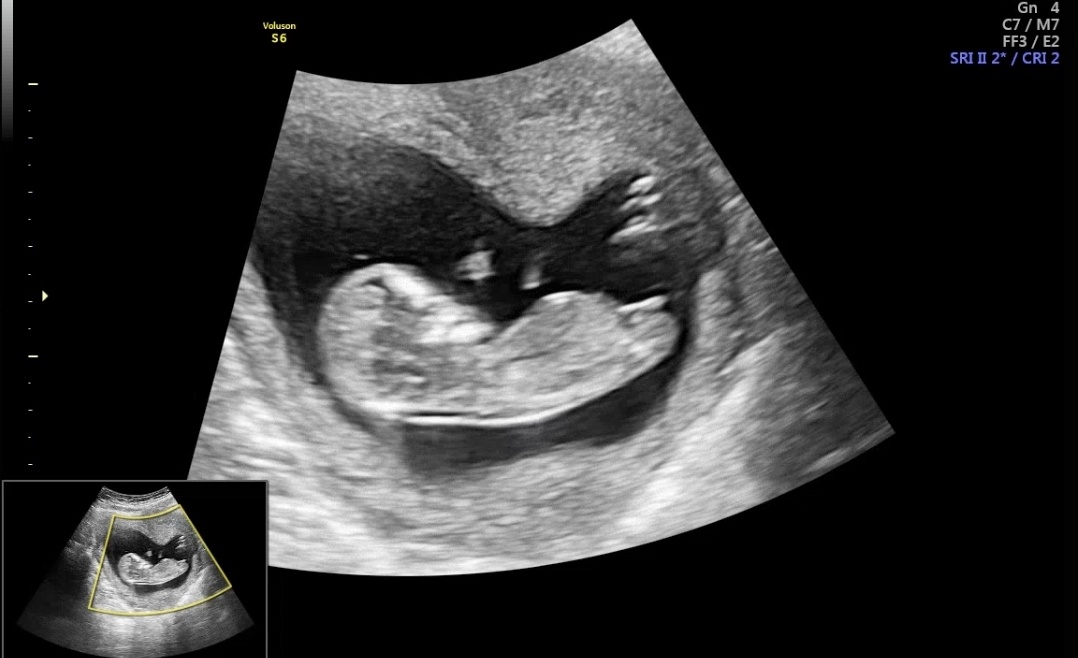

각도법 봐주실분

12주때 사진입니다

이정도 각도는 아직 모르겠어요